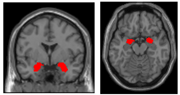

大脳半球外側面の前方部に位置する領域で、意思決定や情動など重要な機能に関与している(右図の赤い部分)。 元の記事へ